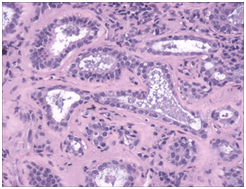

- Lymph node inclusions of mammary gland origin may be composed of deformed mammary gland ducts with divergent morphology and a dual cell population comprising of luminal cuboidal /columnar epithelial cells and basal cells depicting myopithelial differentiation (Figure 1).

- Mammary Inclusions: Axillary lymph nodes may frequently depict the ectopic mammary tissue. Inclusions of the breast tissue are demonstrated as mammary ducts in the subcapsular region. The cellular components described are the epithelium, myoepithelium and apocrine cells. Cystic spaces lined with low, uniform cuboidal epithelium lacking mitosis, hyperplasia or hyperchromasia may be evidenced.4 A singular layer of cuboidal epithelium interlining the tubules (hobnail appearance) or epithelial inclusions situated within or beneath the lymph node capsule may also be elucidated. A distinction is required from a metastatic breast carcinoma. The inclusions may delineate three categories i) glandular structures only ii) squamous cysts only iii) a combination of glandular and squamous epithelium.5

Figure 3 Benign mammary inclusions with glandular configuration.